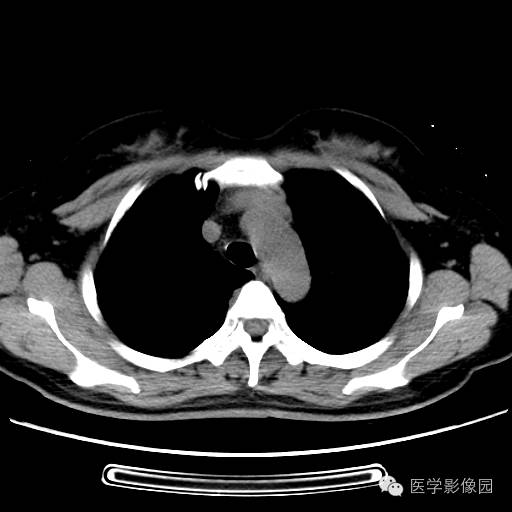

肺叶实变性支气管肺泡癌1例CT影像表现